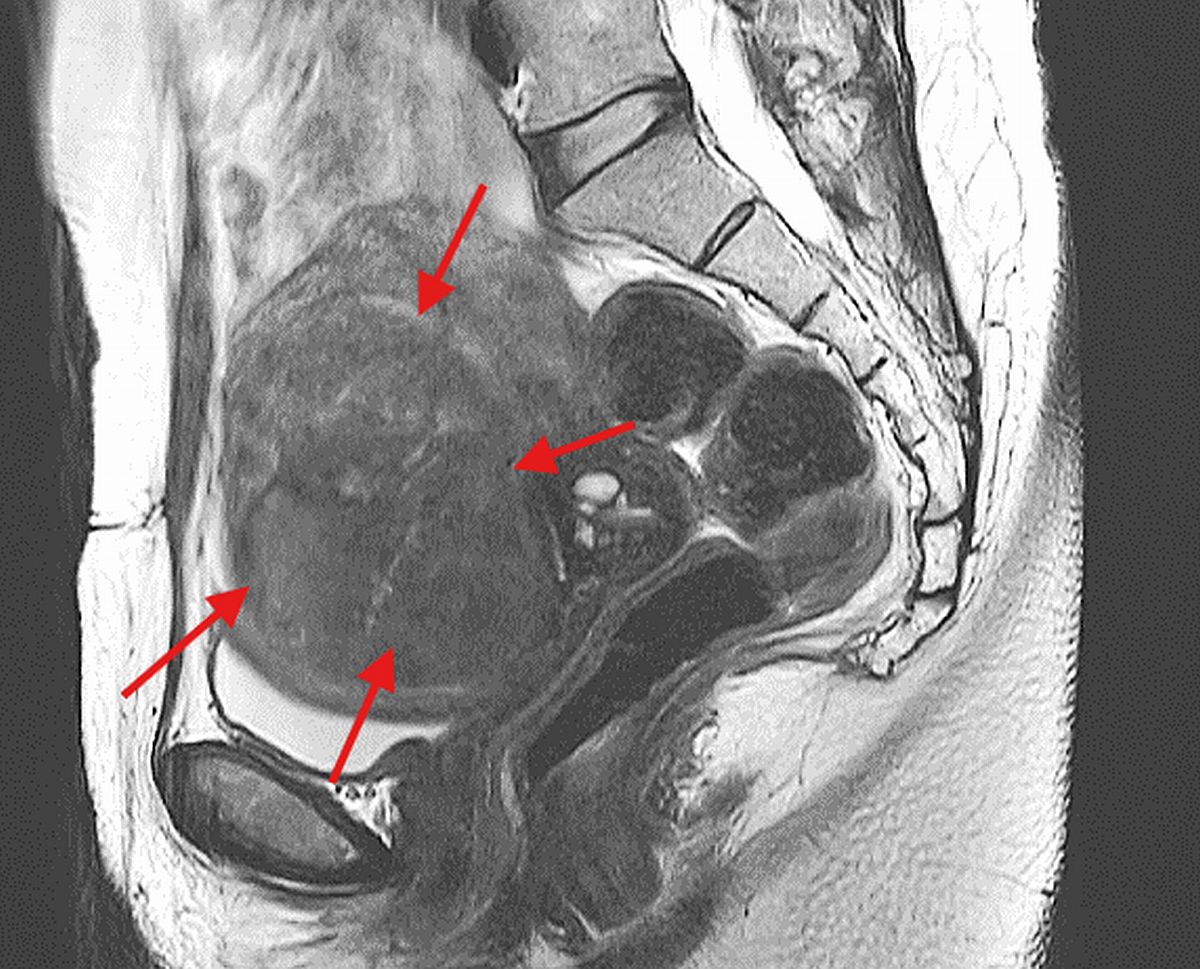

UAE, also known as uterine fibroid embolisation (UFE), is a minimally invasive procedure used to treat symptomatic uterine fibroids by cutting off their blood supply.

“By blocking the blood flow to fibroids, we essentially starve them, causing them to shrink and significantly alleviating symptoms,” shared Dr Tang.

Promising results are also achievable in treating the commonly neglected adenomyosis, a condition often misdiagnosed as fibroids where the inner lining of the uterus (endometrium) grows into the muscular wall, causing severe pain, heavy bleeding, and an enlarged uterus.